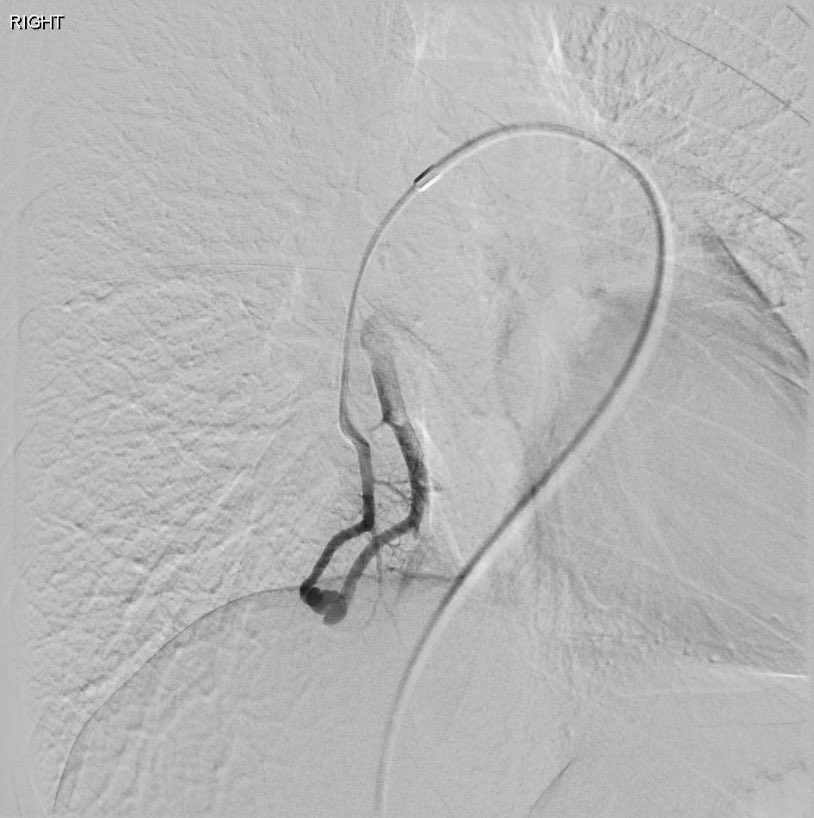

David Léon MD@IdCathThat·

Pulmonary AVM embolization in a patient with HHT using MVP and Ruby coils

David Léon MD tweet mediaDavid Léon MD tweet mediaDavid Léon MD tweet mediaDavid Léon MD tweet media

English